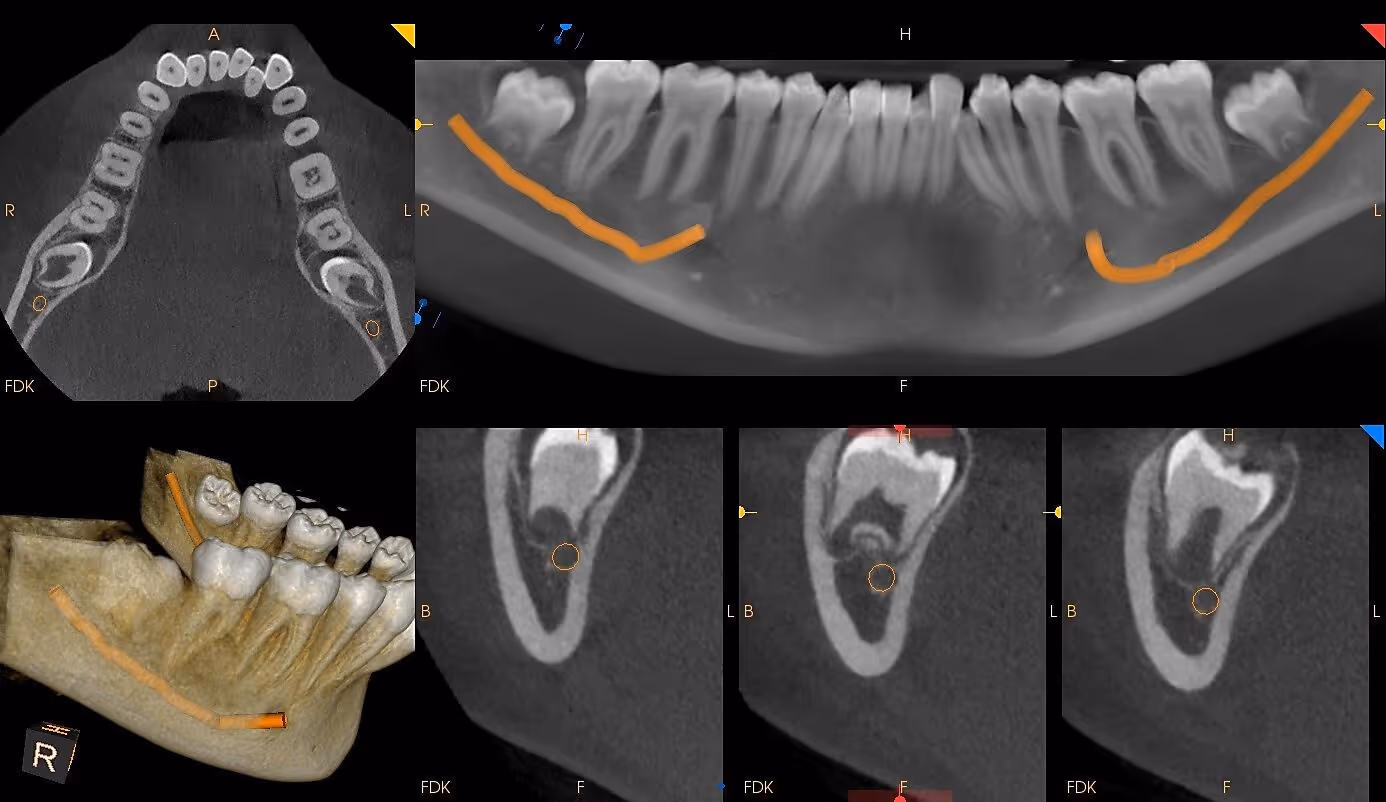

If you’ve ever had traditional dental X-rays, you know they offer only flat, two-dimensional snapshots. CBCT, however, creates a complete 3D image of your teeth, jawbone, nerves, sinuses, and airway—revealing details that are impossible to see on standard X-rays.

CBCT gives your dentist information that cannot be seen on regular X-rays—such as hidden infections, fractures, impacted teeth, cysts, or bone defects. The earlier these issues are detected, the easier they are to treat.

More Precise Root Canal Treatment

Tiny hidden canals and infections are visible in 3D, allowing your dentist to treat the tooth more effectively and reduce retreatment. Also, infections/ abscess around the apex of teeth that are not shown easily on 2D x-rays are readily visible on CBCT imaging leading to more accurate diagnosis.